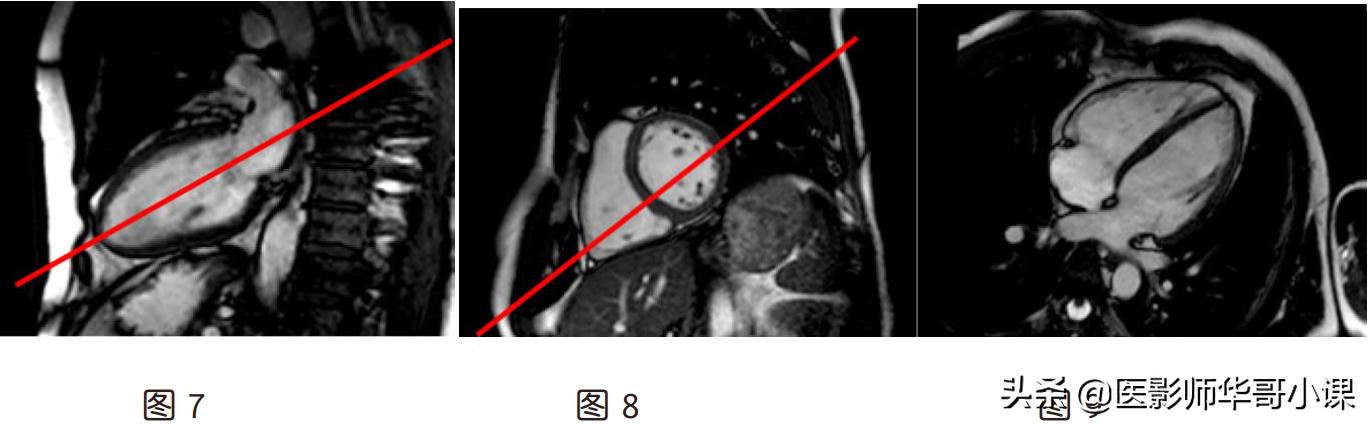

(5)斜矢状左室流出道(图 15):左室短轴位最基底层面平行于左室腔和主动脉根部连线,

左两腔层面平行于心尖和二尖瓣口中点连线

(6)斜冠状左室流出道(图 17):垂直于矢状位左室流出道,平行于主动脉